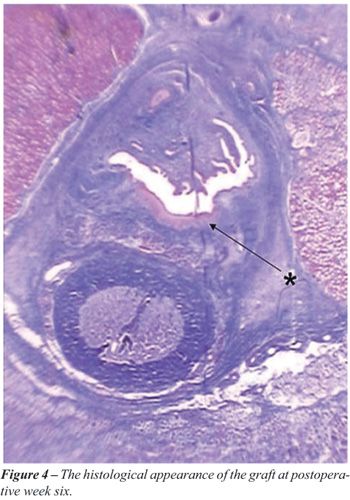

Three weeks after surgery extensive neovascularity was evident in the subepithelial layer with a streaming of fibroblasts toward the graft (Figure-3). Complete disappearance of the polymorphonuclear cells, representing resolution of the inflammatory reaction was evident by 6 weeks postoperatively. The histological appearance of the graft at postoperative week 6 is shown in Figure-4.

The typical squamous epithelium of buccal mucosa and minimal inflammatory cell infiltration in the subepithelial tissues were observed in all rabbits at the grafted buccal mucosa six weeks after surgery. Minimal fibrosis was observed. Microscopically the junction of the graft and normal urethra was identifiable in all groups. Six weeks after surgery retrograde urethrograms confirmed the maintenance of a wide urethral caliber without any signs of stricture or extravasation (Figure-5).